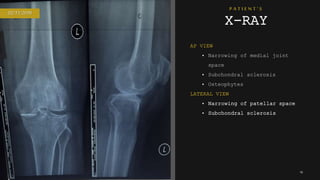

AP VIEW

• Narrowing of medial joint

space

• Subchondral sclerosis

• Osteophytes

LATERAL VIEW

• Narrowing of patellar space